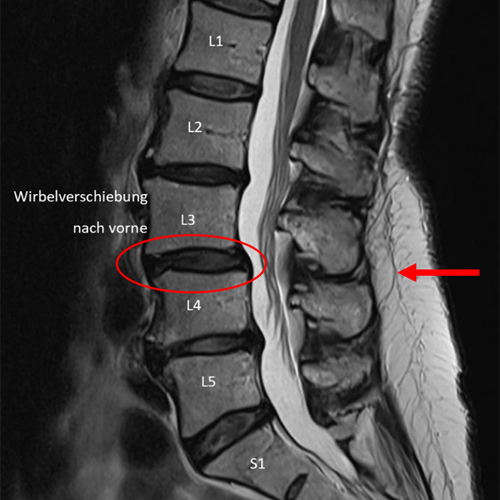

1. Beispiel – Wirbelverschiebung nach vorne

Vergleicht man die Messung der Medi Mouse mit der MRI-Aufnahme der Lendenwirbelsäule der gleichen Patientin, kann man erkennen, dass die Höhe der Knickstellung, welche ihre Ursache in der Wirbelverschiebung nach vorne hat, beim gleichen Segment detektiert wurde.

Wirbelverschiebung MRI